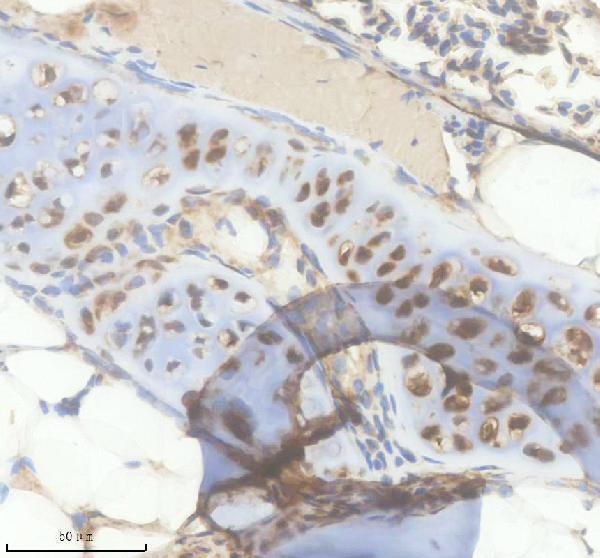

Facts about Interleukin-4.

It induces the expression of class II MHC molecules on resting B-cells. It enhances both secretion and cell surface expression of IgE and IgG1.